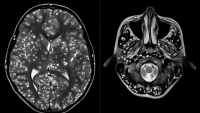

Tras practicarle una resonancia magnética y exámenes de ultrasonido, los especialistas encontraron que la corteza cerebral y el tronco encefálico del paciente estaban llenos de larvas.